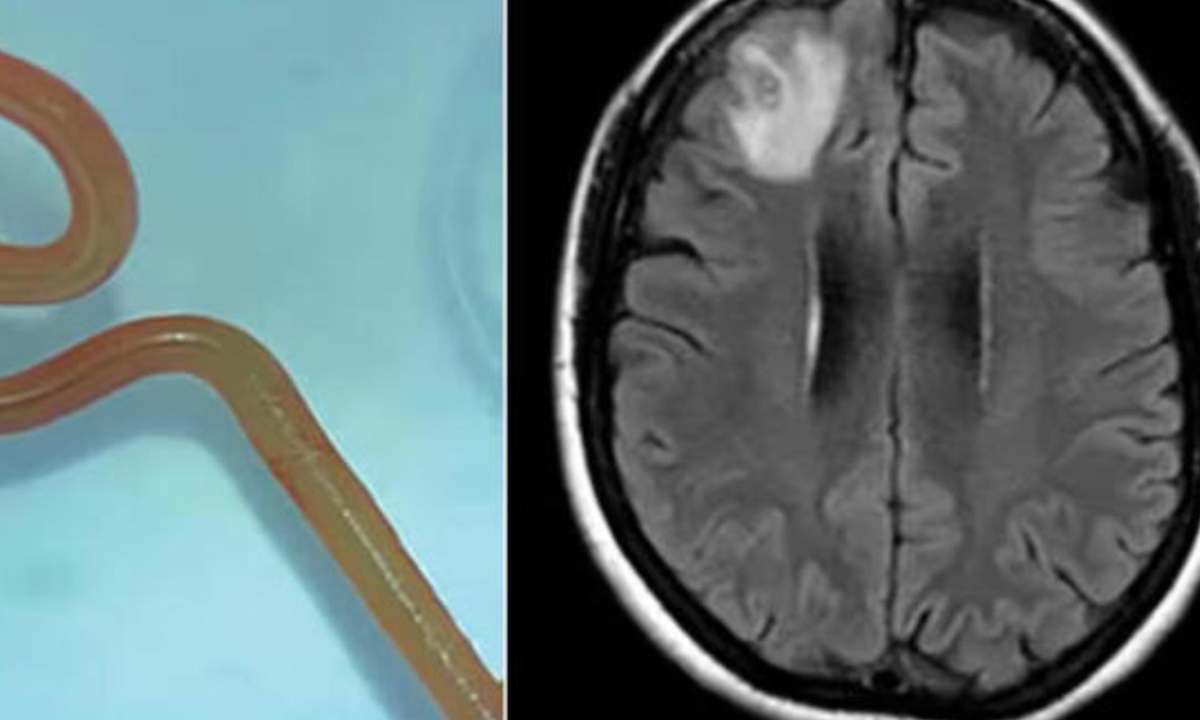

PECHINO – Soffriva di convulsioni e forti mal di testa. Finchรฉ un esame approfondito non ha chiarito la causa: una tenia di 25 centimetri. Ovvero un verme solitario che perรฒ si era annidato nel cervello. Come puรฒ succedere, anche se molto raramente. E’ successo in Cina a una ragazza di 24 anni. Dati i sintomi inizialmente iย medici avevano prescritto a Li Fang alcuni antidolorifici che perรฒ non hanno avuto molta efficacia.

Ma un esame piรน approfondito ha portato alla scoperta di un granuloma che, una volta estratto, ha rivelato qualcosa di ancora piรน sorprendente. Si trattava di una tenia di 25 centimetri che premeva sui nervi e da qui le terribili convulsioni. Ma com’รจ possibile che una tenia si formi nel cervello? In alcuni, rarissimi casi, puรฒ accadere. La colpa probabilmente รจ dell’abuso di carne poco cotta con molti ingredienti aromatizzanti, cosa che ha portato allo sviluppo di questo lunghissimo verme.